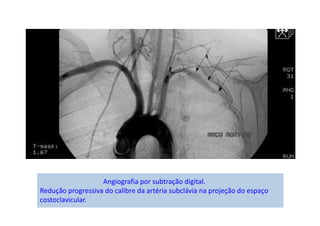

Angiografia mostrando compressão de artéria subclávia em posição neutra

(A), que se acentua com a abdução (B), artéria subclávia direita pérvia em

posição neutra (C) e com compressão à hiperabdução (D).

Cianose de mão esqueda + lesões isquêmicas de polpas

digitais (setas).

Angiografia por subtração digital.

Redução progressiva do calibre da artéria subclávia na projeção do espaço

costoclavicular.